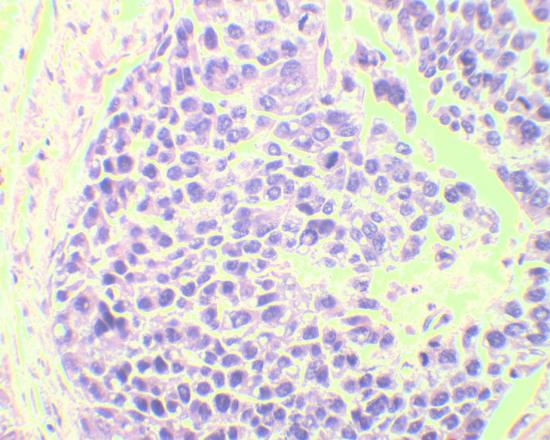

肝癌病理图片

首先,应重视肝组织病理学检查:虽然通过肝脏穿刺取肝组织做病理学检查一直被认为是诊断肝癌的金标准,但仍有许多患者对这种检查手段存在一定的恐惧心理。肝癌诊断包括哪些内容呢?需要说明的是,在CT或B超引导下进行的肝穿刺是比较安全的,而且有些患者只有通过做肝组织病理学检查,才能明确是否患了肝癌。